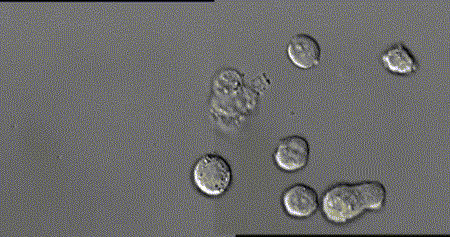

下圖為抗體辨認出細菌(Bacteria)後,包圍、吞噬及消滅細菌的過程。

下圖的上方為入侵身體的抗原,下方為人體特有的抗體,可以看出是因為抗原-抗體結構上的吻合,造成專一辨認的結果。